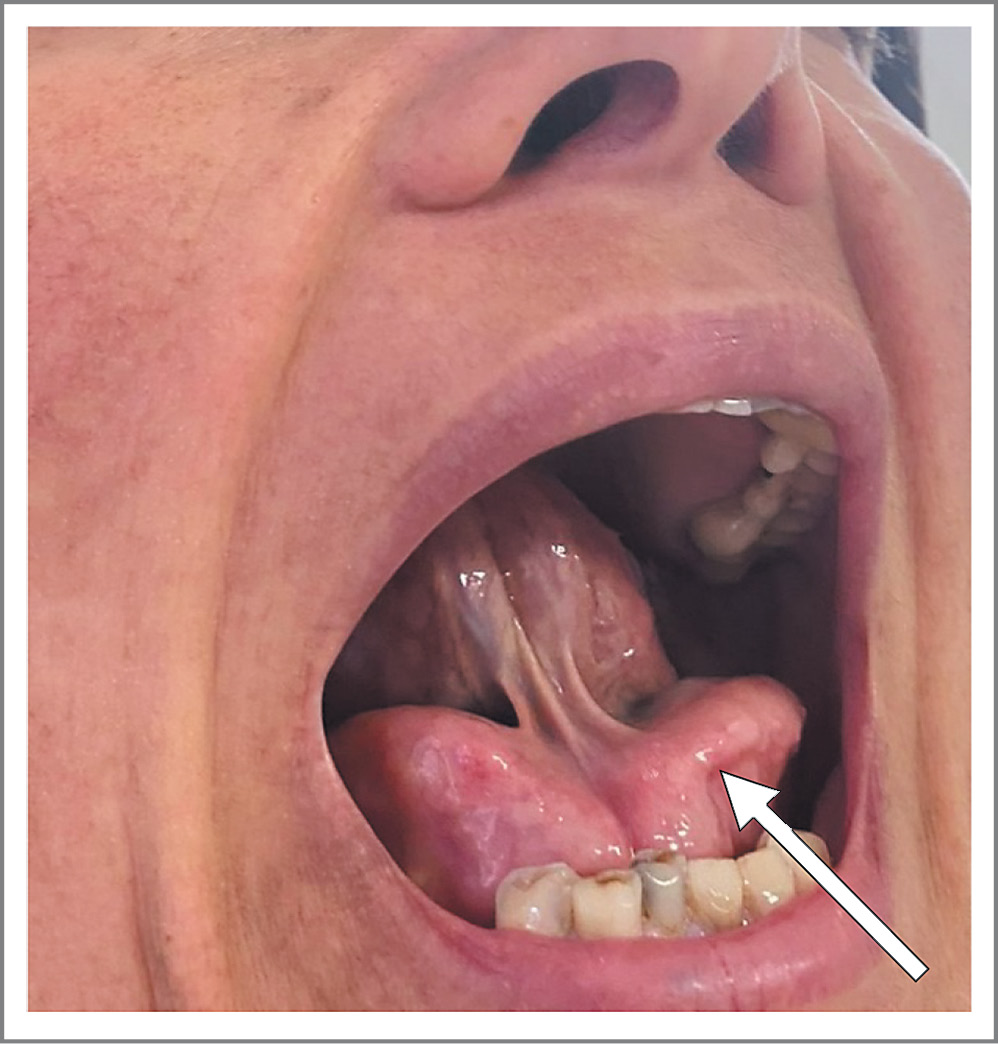

У пациентки Д. 48 лет в 2018 г. появилось образование в подъязычной области, которое увеличивалось в течение 3 лет (рис. 3). Кроме того, отмечено увеличение размеров подчелюстных слюнных желез и слезной железы справа. Заболевания соединительной ткани, в том числе IgG4-ассоциированные, исключены. В сентябре 2022 г. пациентка обратилась в ФГБУ «НМИЦ гематологии».

Рис. 3. Мягкотканные новообразования в подъязычной области.

Fig. 3. Soft tissue neoplasms in the hyoid region.